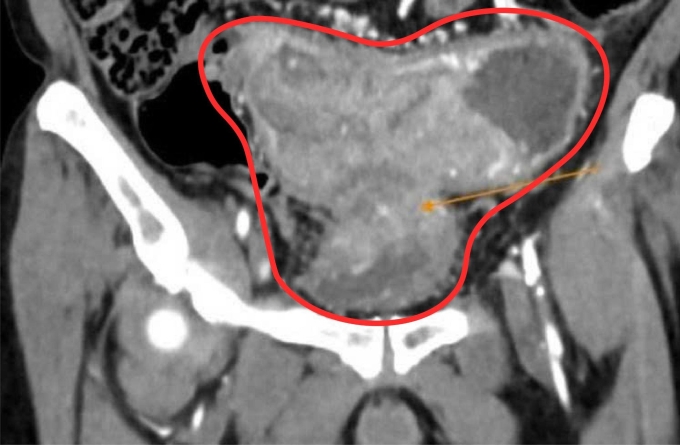

Ông về nhà uống thuốc nam theo liều lượng mỗi ngày ba bát thuốc sắc, kiêng ăn thịt. Táo bón ngày càng nặng hơn, ông sụt 15 kg, không ăn uống được, đau chướng bụng. 6 tháng sau, ông quay lại bệnh viện, chụp CT bụng ghi nhận khối u ác tính gây hẹp hoàn toàn lòng ruột dẫn đến ứ phân, dày thành bàng quang. Gan có hai tổn thương do u đại tràng di căn đến.

Ảnh chụp CT ghi nhận khối u ác tính gây hẹp lòng ruột, dày thành bàng quang bệnh nhân. Ảnh: Bệnh viện Đa khoa Tâm Anh

BS.CKII Nguyễn Trần Anh Thư, khoa Ung Bướu chẩn đoán ông Minh bị ung thư đại tràng sigma (đoạn ruột cuối cùng, có hình chữ S trước khi nối với trực tràng) giai đoạn 4, xâm lấn bàng quang, di căn gan. Ông Minh được phẫu thuật nội soi làm hậu môn nhân tạo, tiếp đến dùng thuốc trúng đích kết hợp hóa trị theo phác đồ FOLFOX (phối hợp ba loại thuốc).